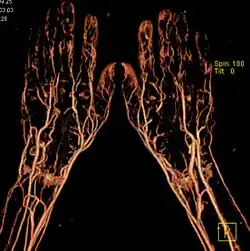

- Angiographie (Darstellung der Gefäße allgemein)

- Arteriographie (Arterien)

- Phlebographie/Venographie (Venen)

Vorteile der CT: Überlagerungsfreie Schnittbilder mit sehr hoher Detailauflösung, v. a. bei knöchernen Strukturen, z. B. Innenohr. Moderne Geräte, sogenannte Mehrzeilenscanner ermöglichen zum Teil bei Kontrastmittelanwendung eine Darstellung auch mittlerer und kleinerer Gefäße, z. B. Herzkranzgefäße. Kurze Aufnahmezeiten, mit und ohne iodbasierte Kontrastmittelgabe, erschließen auch den Magen-Darm-Trakt der bildlichen Darstellung, sogenannte virtuelle Endoskopie. Größter Nachteil der CT: Relativ hohe Belastung mit potenziell schädlichen Röntgenstrahlen, besonders bei den aufwendigeren Untersuchungen. Diese negative Eigenschaft des CT fällt vor allem im Vergleich zum strahlenfreien MRT ins Gewicht.